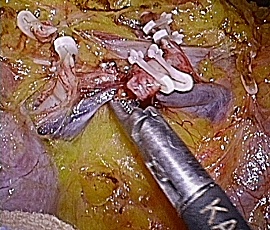

腹腔鏡下胆嚢摘出術の実際

全身麻酔をかけた状態で手術を行います。腹腔鏡下手術では腹部に4カ所の穴、単孔式

腹腔鏡下手術では1カ所の穴を開け、炭酸ガスをおなかの中に入れ、その穴から内視鏡

や手術鉗子を挿入し、画面を見ながら胆嚢を摘出する方法です。

単孔式腹腔鏡下胆嚢摘出術

腹腔鏡手術で胆嚢の摘出と総胆管結石の摘除を同時に行います。胆嚢摘出後、十二指腸

上部総胆管を切開し、胆道鏡を用いて直視下に胆石を除去します。

採石後は胆道鏡で結石遺残のないことを確認します。その後胆管切開部を腹腔鏡下に

体内で結紮縫合を行い、閉鎖します。